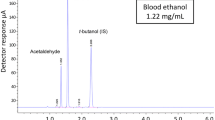

The UHPLC–MS/MS system comprised of a Shimadzu MS 8030 quadrupole mass spectrometer (Melbourne, Australia) operated in electrospray ionization negative mode. A Shimadzu Nexera UHPLC system (Melbourne, Australia) consisted of a degasser, two eluent pumps, a column oven (30 °C) with a Kinetex C18 column (3.0 × 150 mm, 2.6 μm from Phenomenex, Melbourne, Australia), and a chilled autosampler (4 °C). The mobile phases consisted of 50 mmol/L aqueous:ACN (90:10) ammonium formate pH 2.8 (eluent A) and ACN containing 0.1 % formic acid (eluent B). The flow rate of the mobile phase was 0.5 mL/min and was degassed by the integrated Shimadzu Nexera degasser during use. The gradient was programmed as follows: 0–0.5 min hold at 50 % eluent B; 0.5–6.0 min eluent B increasing to 60 %; 6.0–9.5 min eluent B increasing to 75 %; 9.5–10 min eluent B hold at 75 %. Before the start of batch analysis and before each injection, the UHPLC system was flushed for 2 min (90 % eluent B) and equilibrated at starting conditions (50 % eluent B) for 5 min.